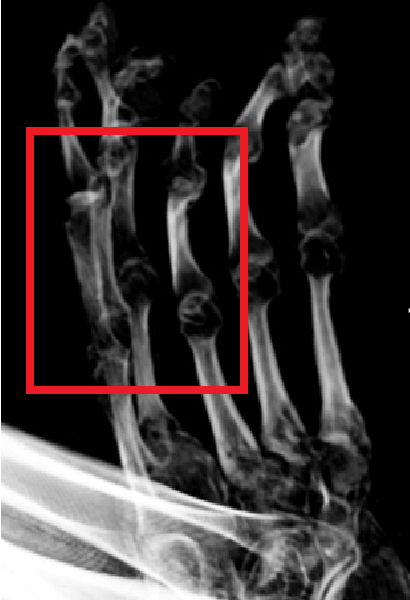

@gchavez101 @JosephAPWilson1 In this scan of "Maria" you can see the the extensor tendons running along the dorsal surface of the wrist and metacarpals. If this mummy really had only three fingers, why is there a fourth extensor tendon visible where a normal human thumb should be located?

@TonyTrupp @GGSH099 @tridactyls In these image of Maria's hands you can see how they inserted extra bones to make the fingers longer - just as they did with the feet. But they were sloppier with the orientation of some of them!

When some who really understands human anatomy analyses these supposed alien mummies it becomes even more apparent that they removed a couple digits from a human hand to make it three fingered.